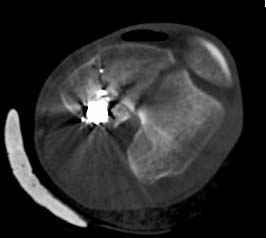

У молодого человека огнестрельное слепое ранение н/3 правого бедра. Поступил в клинику с внутрисуставным многооскольчатым Т-отразным переломом дистального отдела бедренной кости. Дополнительно на СТ-исследовании обнаружен перелом внутреннего мыщелка Hoffa со смещением.

Больной взят в операционную на второй день, где из небольшого медиального доступа выполнена артротомия коленного сустава. Произведена репозиция отломков, фиксация винтами. Попутно удалена пуля. Первым делом была достигнута репозиция медиального мыщелка (перелома Hoffa, где коронарная плоскость перелома трудно поддается закрытой репозиции и фиксации. ) Затем была достигнута идеальная репозиция суставной поверхности бедра и фиксация компрессирующими headless screws.

Дистальный отдел бедра был дополнительно фиксирован buttress пластиной с медиальной стороны из того же разреза. Для усиления фиксации латеральной колонны - с латеральной стороны закрытым способом из минидоступа установлена еще buttress plate. Пулевой канал дополнительно не подвергался хирургической обработке.